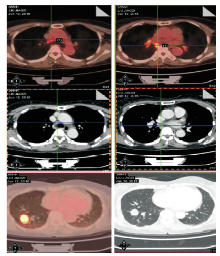

2015-06-12 PET/CT:右肺下叶结节, 大小约2.1 cm× 2.4 cm× 2.1 cm, SUVmax10.3, 区域多发肿大淋巴结(4R、7、10R、11-14R)糖代谢不同程度增高, 考虑右肺癌并区域淋巴结转移, 见图1

图1 2016-06-12 PET/CT 图像